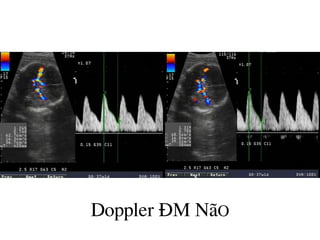

Doppler §M N·O

C¸c lo¹i Dopper:

Doppler liªn tôc

Doppler xung

Doppler mµu

Doppler t¨ng cêng n¨ng lîng

ChØ sè Doppler

-ChØ sè trë kh¸ng ngo¹i biªn

chØ sè Pourcelot: RI =S-D/S

-ChØ sè xung: PI= S-D/M

-ChØ sè Stuart-Drumm:ISD= S/D

-ChØ sè t©m tr¬ng: ID=D/S